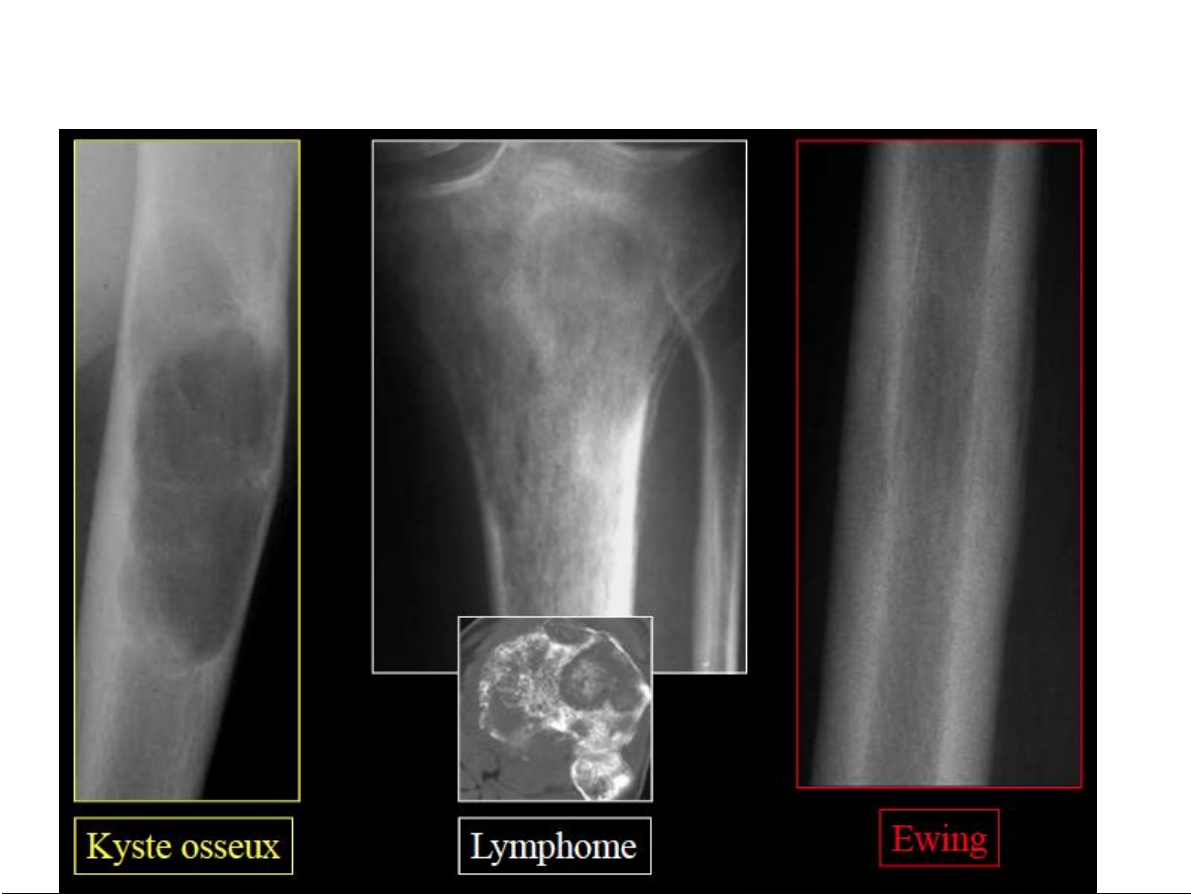

Bất thường về cấu trúc Huỷ xương 1.Giới hạn tổn thương

• Không rõ, vùng chuyển tiếp

rộng tổn thương tiến triển nhanh

• Rõ, vùng chuyển tiếp hẹp lành tính 31-Jan-23 CĐHA Cơ-Xương-Khớp

• Không rõ, vùng chuyển

tiếp rộng tổn thương tiến triển nhanh

• Rõ, vùng chuyển tiếp hẹp lành tính. 31-Jan-23 CĐHA Cơ-Xương-Khớp Huỷ xương 31-Jan-23 CĐHA Cơ-Xương-Khớp Huỷ xương 31-Jan-23 CĐHA Cơ-Xương-Khớp 31-Jan-23 CĐHA Cơ-Xương-Khớp